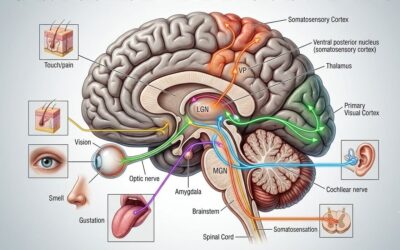

But physiology is not only about state—it’s also about timing.

Circadian rhythms regulate a wide range of biological processes, including hormone secretion, immune function, metabolism, and gene expression.6 When these rhythms are aligned, they support physiological stability. When they are disrupted, the effects extend far beyond fatigue.

The Nervous System, Inflammation, and the Microbiome

The autonomic nervous system adds another layer of complexity.

The balance between sympathetic (“fight or flight”) and parasympathetic (“rest and digest”) activity regulates processes ranging from inflammation to digestion to immune function.¹² Chronic sympathetic activation has been associated with: